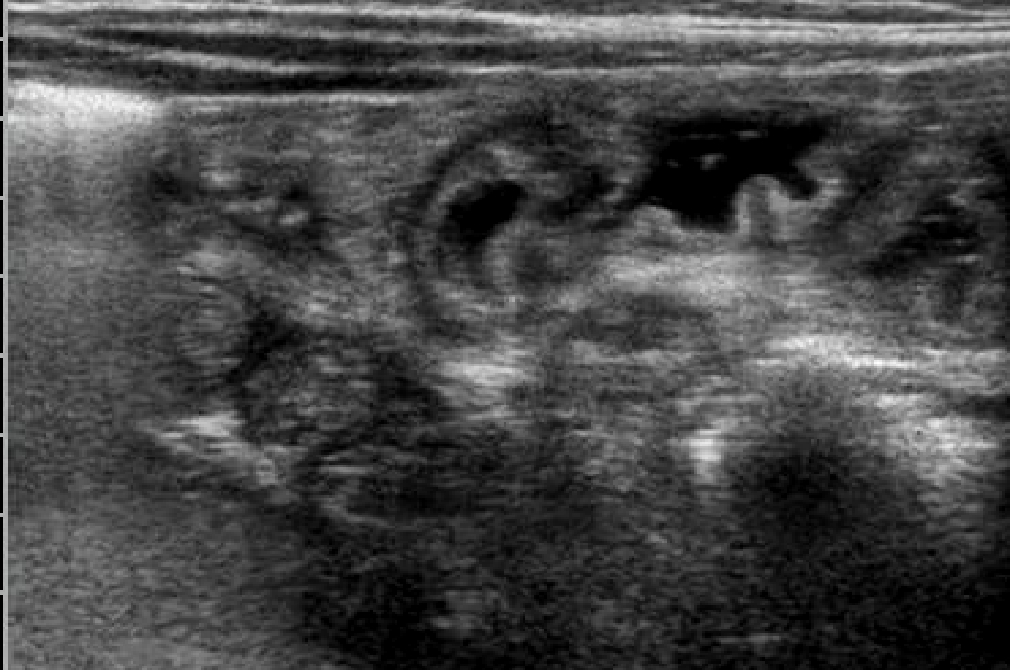

Un'ecografia

addominale conferma un diffuso ispessimento della parete

intestinale e la presenza di una piccola falda ascitica.

(fig.1-2)

Dopo

l'avvio della NP e dell'alimentazione orale con cibi privi di

grassi e proteine assistiamo ad una rapida normalizzazione del

quadro ecografico intestinale con normalizzazione dello spessore

di parete e risoluzione del versamento ascitico (fig.5-6)

Normalizzazione del quadro con riduzione dello spessore di parete e risoluzione del versamento ascitico